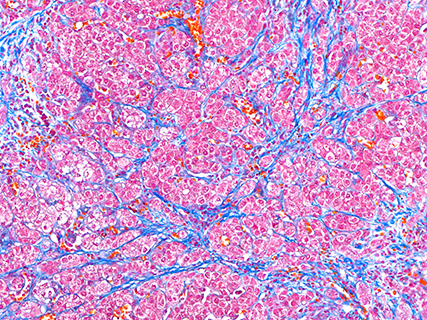

Azan staining (mouse liver)